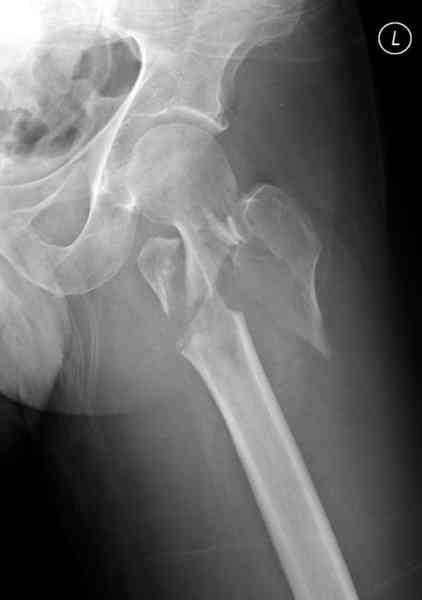

Re: [1/3] Перелом проксимального бедра

Применили проксимальную Synthes Locking plate, из-за множественных фрагментов посчитали более приемлемым в этом случае (клиника университетская, резиденты должны имет возможность созерцать разные варианты остеосинтеза).

Также старался минимизировать доступ на уровне перелома с субвастус доступом, диафиз фиксирован перкутанно, не стали гонятся за малым вертелом, как смог зафиксировал.

Перелом из четырех фрагментов, не стабильный (лекция Michael R. Baumgaertner, http://www.hwbf.org/ota/bfc/baumg/exp.htm), нужна стабильная фиксация.

Фиксация таких нестабильных чрезвертельных и reverse obliquity субтрохантерик переломов всегда была сложной задачей и ранее использовали Blade Plate. Но многие локальные общие ортопеды, к которым, в основном поступают такие больные, имели трудности с применением импланта, где необходимо было точная калькуляция по введению Blade и поэтому Synthes разработал Proximal Locking plate как альтернативу, где три проксимальные шурупа в разных направлениях создают концепцию угловой стабильности Blade Plate.

Со второго дня движения в суставе, контрольный осмотр через две недели и в зависимости от рентгенологического сращения, дозированную нагрузку с постепенным увеличением начнем через 5-6 недель.